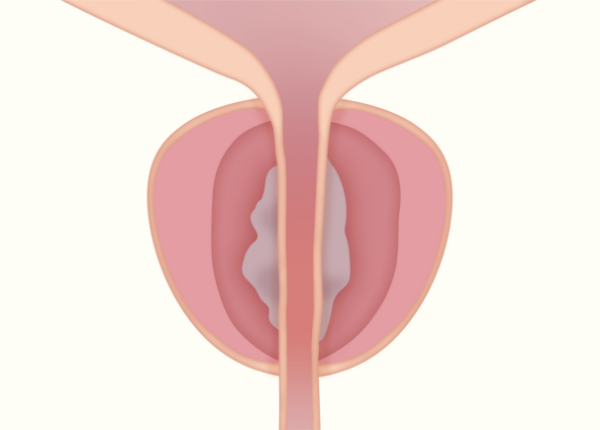

Rezumシステムは、内視鏡を用いて尿道から入り、水蒸気を利用して前立腺肥大症を治療する医療機器です。

肥大した前立腺組織内に103℃の水蒸気を9秒間噴霧し、組織を約70℃まで上昇させることで組織を壊死させます。

従来の前立腺肥大症に対する温熱療法と比べて、水蒸気を利用しているため対流によってムラのない治療効果が発揮され、尿道粘膜や性機能温存が可能です。

治療・手術時間は5〜15分程度で、治療効果は約2週間後から徐々に認められ、長くても約3カ月後には排尿状態の改善が期待できます。